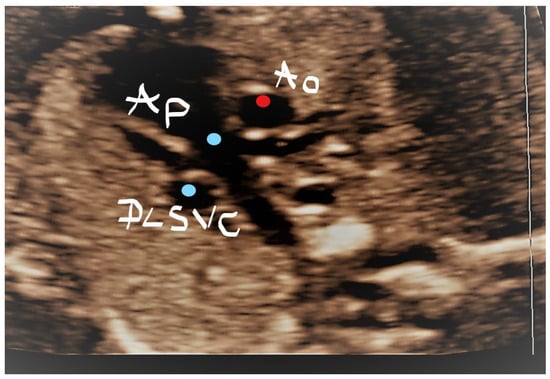

4.4. Case 4